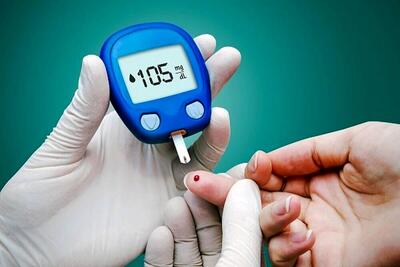

اسامی معجزههای کاهش قند خون

قند خون بالا یا هیپرگلیسمی میتواند باعث عوارض طولانی مزمنی مانند بیماریهای قلبی عروقی، آسیب عصبی، عفونت لثه و حتی مشکلات چشمی شود. هیپرگلیسمی همچنین میتواند به رگهای خونی آسیب برساند و در نتیجه، احتمال بیماری قلبی، سکته مغزی و بیماری کلیوی را افزایش دهد.